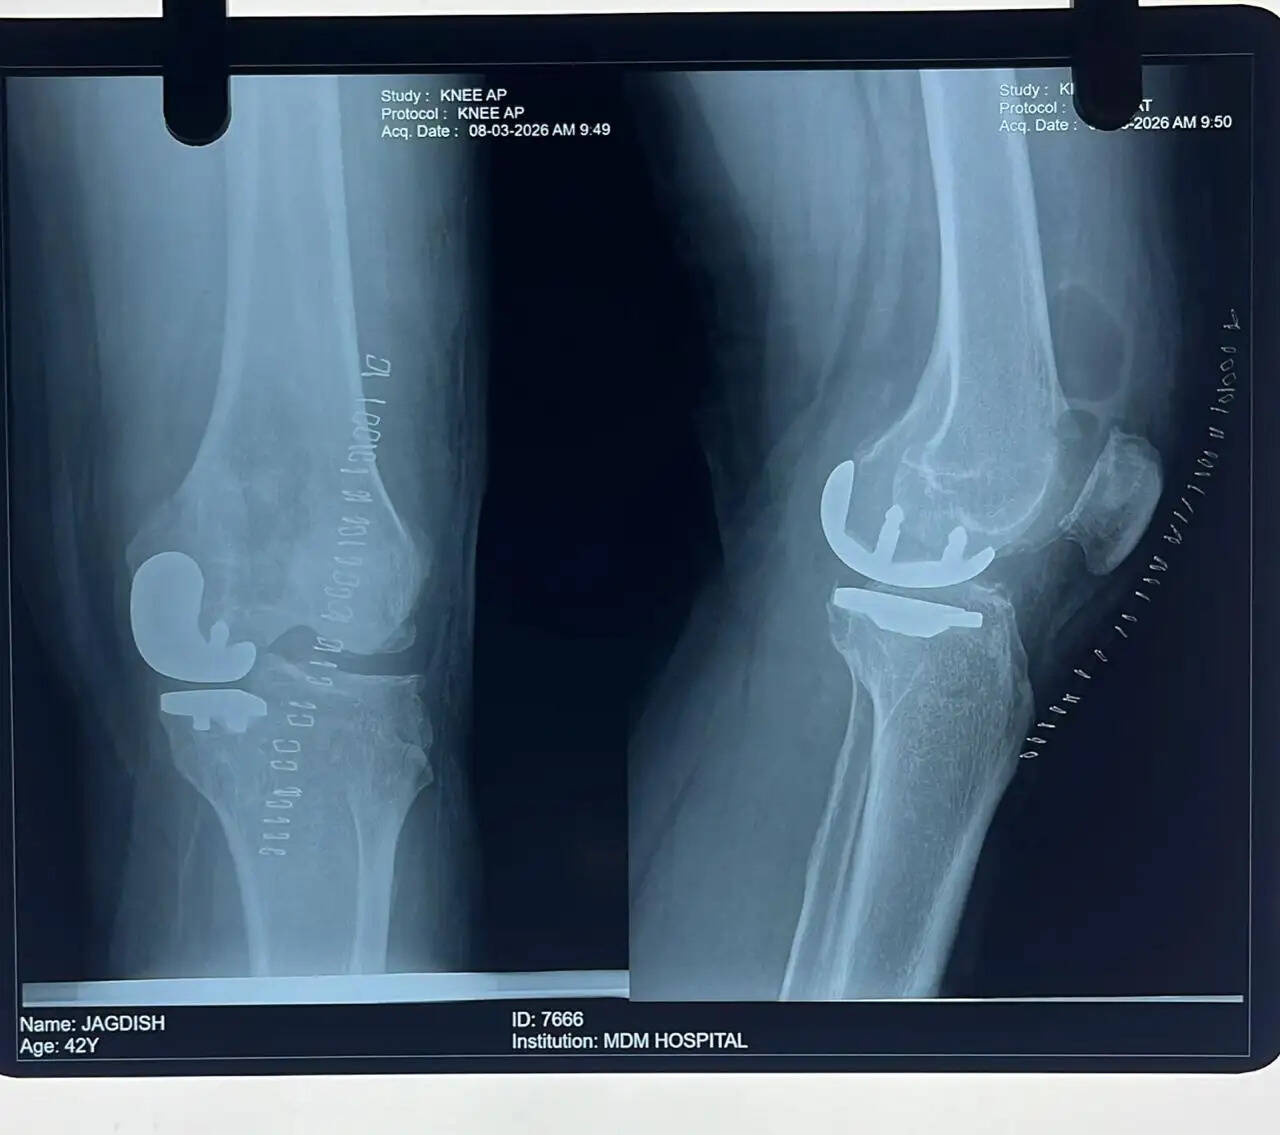

अस्थि रोग विभाग के विभागाध्यक्ष डॉ. अरुण वैश्य ने बताया कि एक मरीज घुटने में दर्द की समस्या लेकर अस्पताल आया था। जांच के दौरान पाया गया कि घुटने के जोड़ के तीन हिस्सों में से केवल एक हिस्सा (मीडियल टिबियो-फेमोरल भाग) में आर्थराइटिस था, जबकि बाकी दो हिस्से सामान्य स्थिति में थे। मरीज की कम उम्र और घुटने के लिगामेंट्स की अच्छी स्थिति को देखते हुए पूरे घुटने को बदलने के बजाय केवल प्रभावित हिस्से का ही रिप्लेसमेंट करने का निर्णय लिया गया। इस प्रक्रिया को यूनिकंडाइलर नी रिप्लेसमेंट कहा जाता है।

डॉ. वैश्य ने बताया कि इस तकनीक से मरीज को घुटना लगभग सामान्य जैसा महसूस होता है। साथ ही यह सर्जरी छोटे चीरे से की जाती है, जिसमें रक्तस्राव कम होता है, दर्द कम होता है और ऑपरेशन कम समय में पूरा हो जाता है। ऑपरेशन के बाद मरीज जल्दी चलने-फिरने में सक्षम हो जाता है।